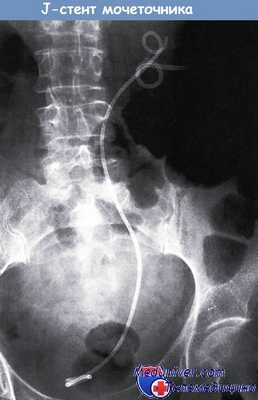

Альтернативные методы включают сцинтиграфию почек после введения фуросемида или УЗИ почек. Если поставлен диагноз двусторонней обструкции мочеточников, до проведения какого-либо вмешательства необходимо провести срочное обследование больной, чтобы определить точный размер злокачественного новообразования. При местном распространении злокачественной опухоли и отсутствии метастазов устранить обструкцию мочеточников можно с помощью цистоскопии и стентирования мочеточника.

Если стентирование было безуспешным, необходимо установить подкожную нефростому (ПКН). В особых случаях, когда невозможно устранить обструкцию, требуется диализ. Через несколько дней после устранения обструкции мочеточников необходимо провести тщательную оценку диуреза и коррекцию баланса электролитов.

Двойной J-стент, введенный в правую почку, мочеточник и мочевой пузырь посредством подкожной нефростомии.